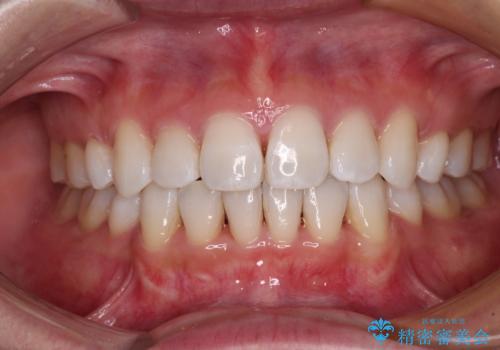

出っ歯を改善 目立たないワイヤー装置での抜歯矯正

- 口元の突出感と口の閉じにくさを気にして来院された患者様です。

上下左右第一小臼歯4本を抜歯し、ワイヤー装置にて口元を引っ込めるよう矯正治療を行うこととしました。

2年~2年半が治療期間の目安でしたが、順調に治療が進み、1年9か月で満足のいく歯列となりました。